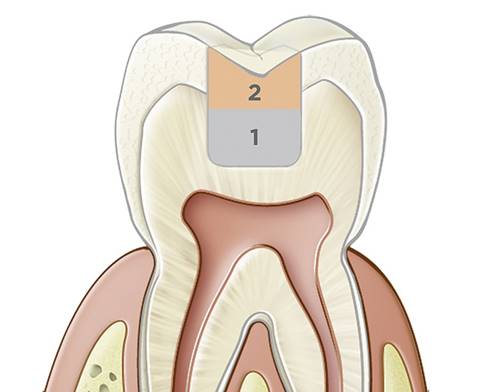

Fig 2. Illustration highlighting the most vulnerable area prone to recurrent decay in Class II restorations: the proximal box. Adapting materials well in this area can be challenging, which is why flowable bulk-fill dentin replacement composites are desirable.

FIgure 2

Ideally an absence of postoperative sensitivity will be long lasting, but immediately preventing postoperative sensitivity does not preclude the future occurrence of microleakage. With resin-based materials, microleakage is inevitable over time due to material breakdown and failure from wear and various intraoral proteases.1,2 The No. 1 reason for composite failure is recurrent decay, and the floor of the proximal box of a Class II restoration is the most vulnerable area (Figure 2).1,2

To help maintain marginal integrity and prevent microleakage, a low-stress composite adaptation is required at this most vulnerable area, and every attempt should be made to ensure minimal shrinkage stress.2,8 Additionally, particularly for Class II restorations, creating tight contacts is essential and requires well-adapted materials that are tightly and sufficiently packed to ensure good contacts and an ideal emergence angle.2,7 Contacts should be broad throughout the range of tooth structure because it touches the opposing tooth.